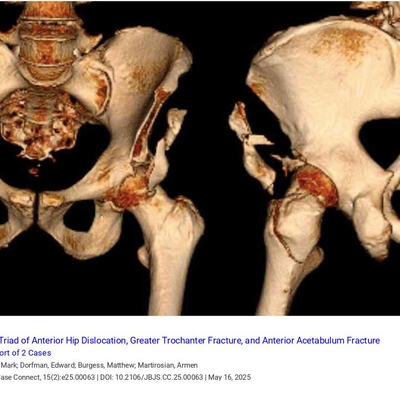

Click on an image below to view more info.